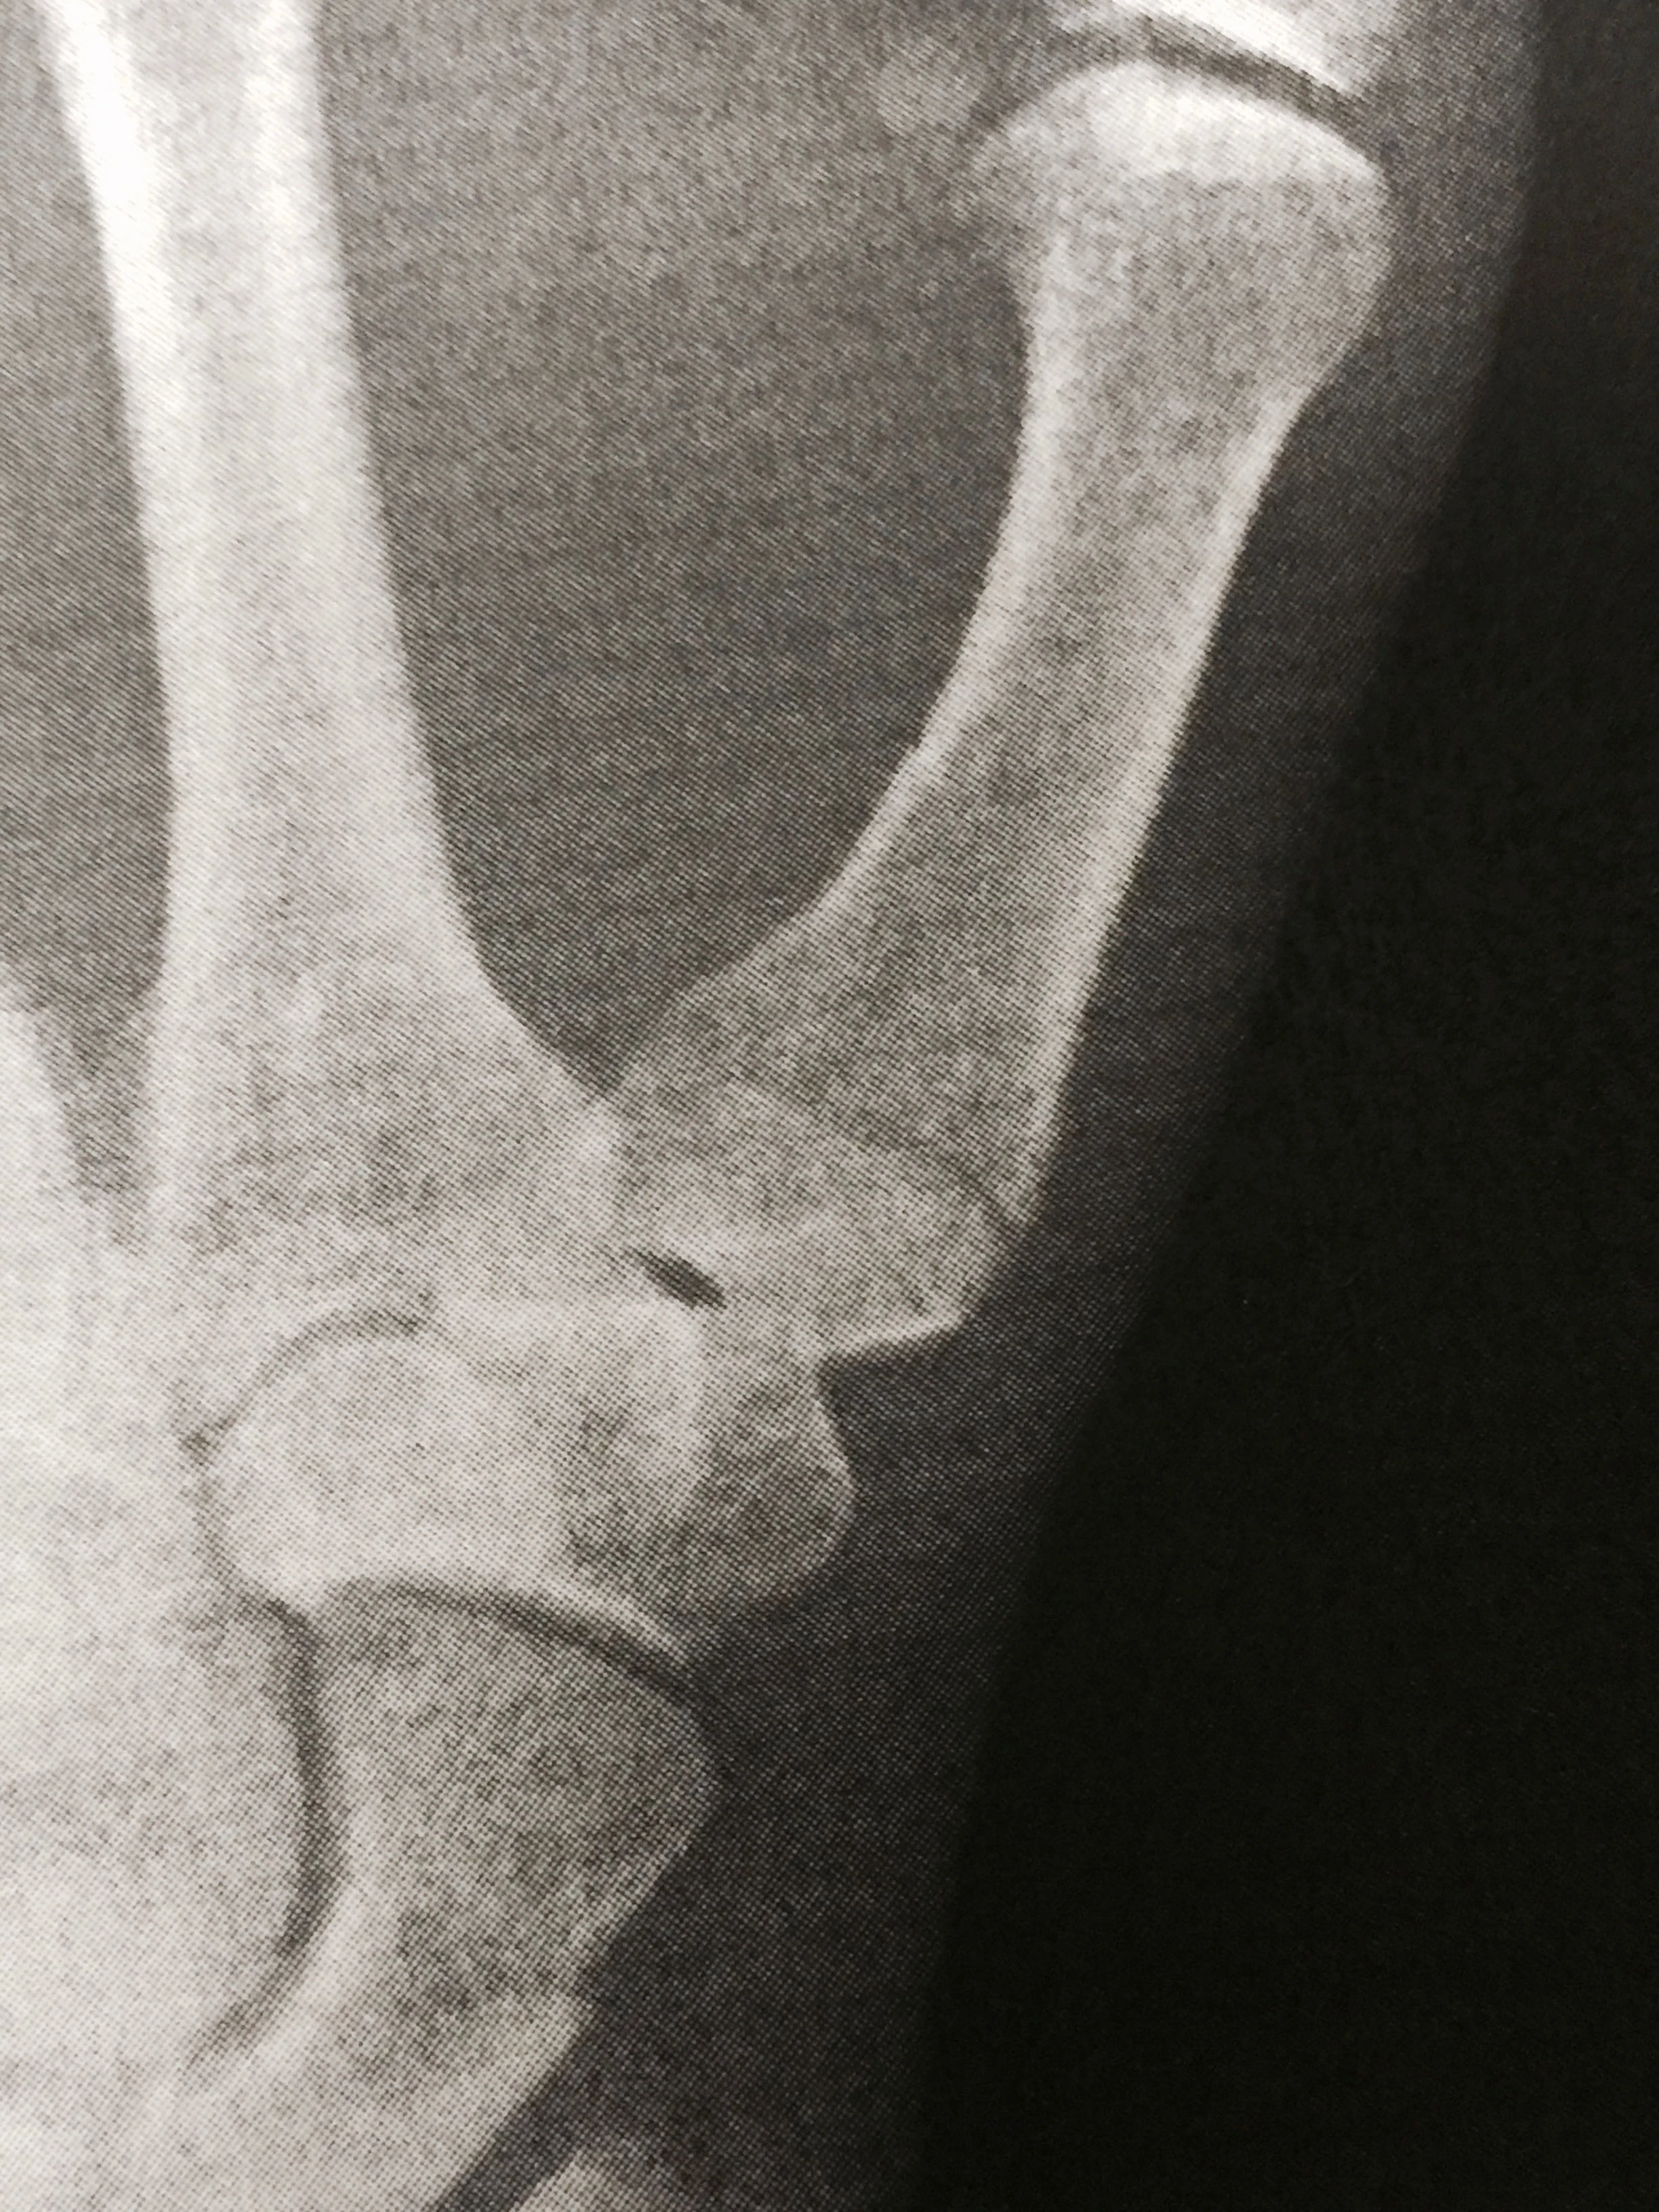

This is the day I am supposed to be racing in Asheville. Actually, all the Master men are racing today. The course is only getting worse, more chewed up with more sketchy sections. That will probably continue throughout the week, and only accelerate with forecasted precipitation. But, alas, I’m not toeing the line today. I went and got my body checked out, after I pre-rode the course and it was pretty much as I already knew. My left thumb is broken, way low on the metacarpal (lowest bone in the thumb, towards the wrist). Plus, I have two bad ribs. I have been teetering back and forth, ever since leaving the doctor’s office, about racing today. I have sort of prided myself in racing busted up a little, but this isn’t the right time for that. I weighed the pros and cons and couldn’t justify it this time. Plus, I’ve hardly slept for two nights straight. Yesterday was a yin/yang day. I felt super, once again, riding over to the course. So, I was stoked. I was having a difficult time holding onto the bars, but it got better as I gripped more. Once I got to the course, the course was open to pre-ride. I rode two laps. I was just barely able to maneuver around the course. Every once and awhile I would hit a dip or root and it would send a shooting pain through my side. That isn’t even addressing the problem holding onto the bars, without the ability to brake with my left hand. So, I went to Blueridege Bone and Joint and got some x-rays. Pretty much exactly what I thought. Ribs are just ribs, but the thumb is something special. It is my “best” thumb, my go to thumb now. My right one is pretty jacked up permanently. I called Stacie and she seesawed back and forth, then finally gave me the go ahead to race. But after thinking about it, overnight, I decided that it just isn’t worth it By worth it, I mean I don’t really have anything to prove here. I’ve been waffling back and forth about this for a while, but now it is pretty clear. This really isn’t a good time to make a bad critical decision. I know what I have achieved in the sport and want I hope to achieve. This isn’t really part of that. Plus, I have plans for my thumb later in my life. Here’s my regret. I regret that I don’t get to ride around this course at race speed. I personally would love to see what this course rides like fast. I have to admit, I am mildly surprised how well I feel riding my bike the last couple days. I sort of lucked out, with some planning, to be riding my bike so quickly just now. So good, I hate to not see what it would be like racing. The course is perfect for me. Hard climbing and technical descents. Plus, heavy field riding. I couldn’t have designed a better course for my current form. So, that is just about the only regret. I made a stupid mistake, so I don’t get the experience. That isn’t a huge cost, really. I think the course is great, but in reality, is too hard for the majority of the riders that are racing here. There are a handful of guys that are talented enough to make use of this course, but for the masses, this course is too challenging. And like I said yesterday, add precipitation to the course and it will become an epic ordeal. I can’t imagine a bunch of juniors racing under those conditions this weekend. There will be much too much off the bike sections to really make it a fair race. And I think the field sections will become a quagmire too, really difficult. So, I’m packing up and heading over to the race this morning, to watch my friend Shadd Smith race. Then I’m getting in my van and driving back to Louisville, hang a night and then on to WIsconsin. I’m not sure whether I can ski or not. I know I should be able to walk around in the Northwoods on snowshoes and enjoy. I sure wish Bromont was around. I miss that dog. This is Dr. Craig Burnworth. He gave me some good insight about my options. He is a long distance trail runner and knows all about racing hurt. The one thing about getting hurt, recently, is running into super guys like him. And this is Marshall Gordon, a guy I met at Starbucks after the casting of my thumb. I was drowning my sorrows in hot chocolate and a chocolate croissant. I predict he wins the Master’s 75+ today. Here is my cast. At least it is removable. Photo of my x-ray. The dark line at the base of the thumb is the fracture. https://www.youtube.com/watch?v=oycgOENyKCQ&feature=youtu.be Here is the whole lap. 6 minutes to 12 minutes is the technical sections.